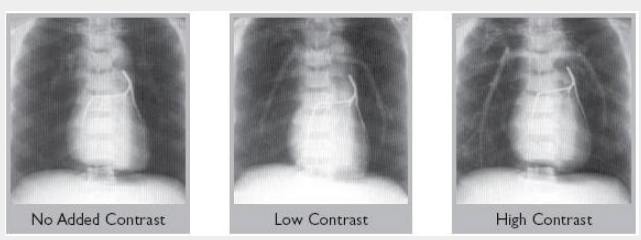

All models are available with blood-equivalent pulmonary arteries, or with low or high contrast media added.

RS-320:Lung/Chest Phantom with removeable diaphragm lung pair insert without coronary artery